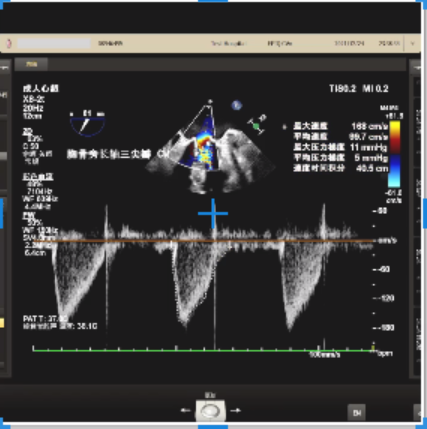

经食道心脏超声结果显示,人工二尖瓣(生物瓣)其中一瓣叶完全脱垂,关闭不全,中度反流,缩流颈宽约4.1mm,反流面积5.5cm²,瓣口峰值流速2m/s,峰值压差16mmHg,平均压差9mmHg。

7.Tee观察无PVL且左向右分流,瓣中瓣植入后观察左房峰值压明显下降,二尖瓣平均跨瓣压差降至5mmHg。